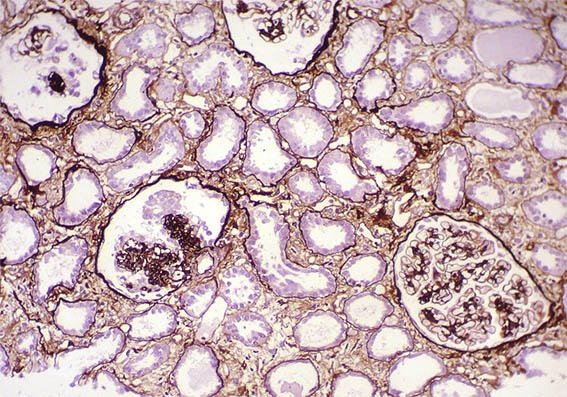

Figure 7. Methenamine-silver, X100.